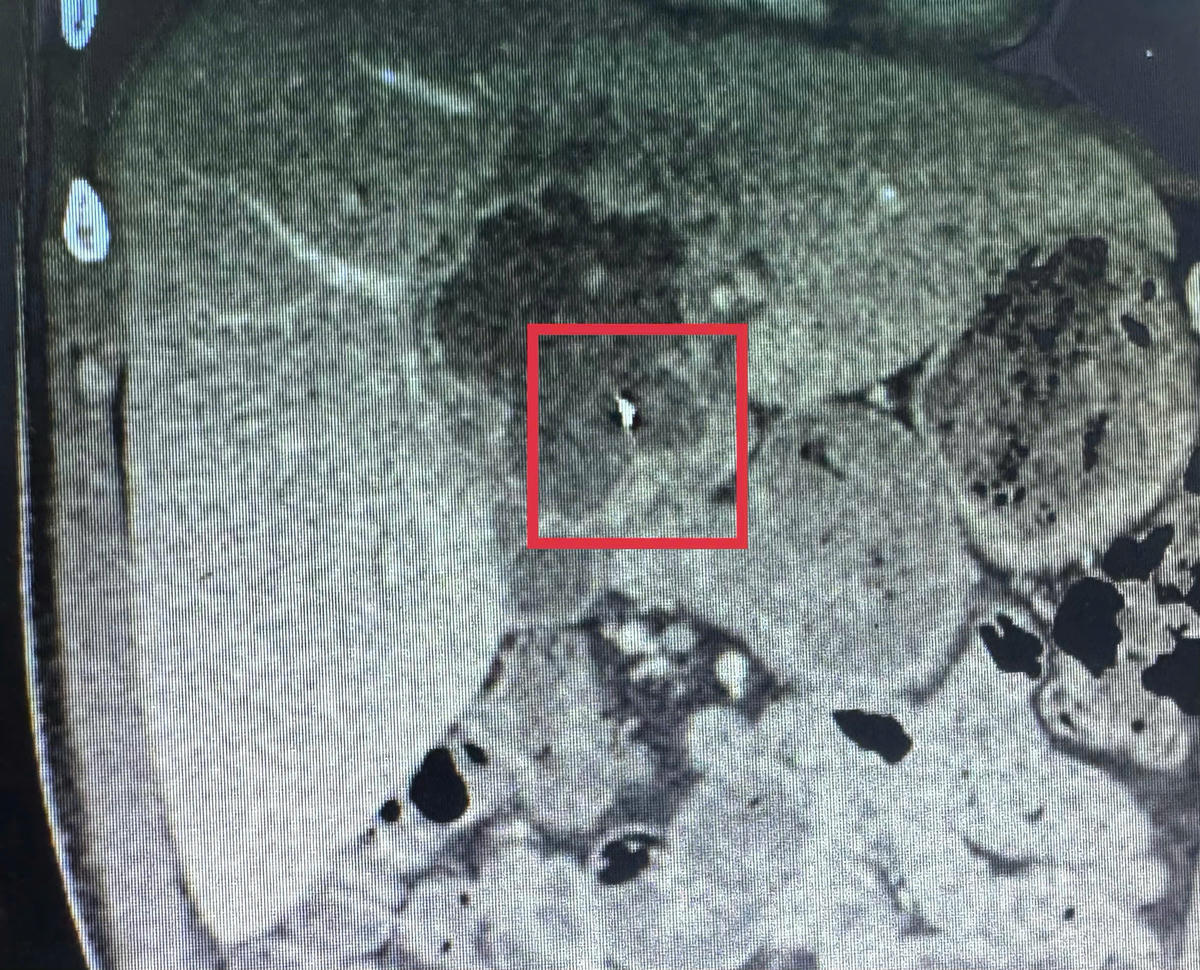

Trước đó, ngày 9/2, bệnh nhân T.T.L (41 tuổi, ngụ xã Nhơn Phú, tỉnh Vĩnh Long) nhập viện trong tình trạng đau dữ dội vùng thượng vị kèm sốt cao. Qua thăm khám lâm sàng, kết hợp siêu âm ổ bụng và chụp CT-scan, các bác sĩ phát hiện ổ áp xe gan kích thước khoảng 5x6 cm, bên trong có dị vật kim loại dài khoảng 6 cm, tình huống hiếm gặp.

Ngay sau khi có kết quả chẩn đoán hình ảnh, bệnh nhân được hội chẩn liên chuyên khoa giữa Ngoại Tổng quát và Chẩn đoán hình ảnh. Các bác sĩ xác định nguyên nhân áp xe gan do dị vật kim loại và chỉ định phẫu thuật nội soi cấp cứu nhằm lấy dị vật, đồng thời kiểm soát ổ nhiễm trùng.